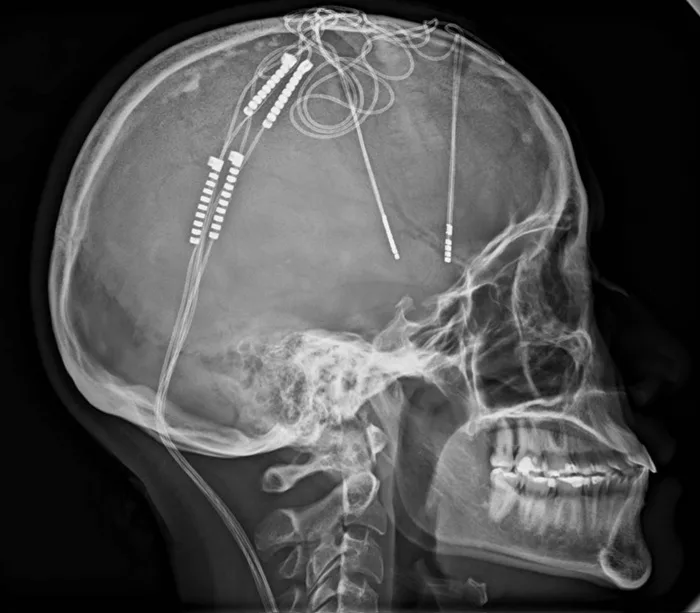

Electrodos contra la depresión, novedoso procedimiento. Foto: HIC

• Tras 17 años con depresión y ansiedad, Lorena Rodríguez recibió en el HIC una Estimulación Cerebral Profunda (DBS) que, por primera vez, incluyó cuatro electrodos en lugar de dos, marcando un procedimiento pionero en el país.

Esta innovadora cirugía consiste en la implantación de pequeños electrodos o ‘chips’ directamente en el cerebro. Estos se conectan internamente a una batería (similar a un marcapasos) que se aloja discretamente bajo la piel, usualmente en el pecho. El dispositivo emite impulsos eléctricos continuos que regulan la actividad cerebral, mientras un control remoto permite, por telemetría (tecnología que permite la medición remota y la transmisión inalámbrica de datos), gestionar y ajustar la intensidad de estos impulsos con precisión de acuerdo a la necesidad de la paciente.